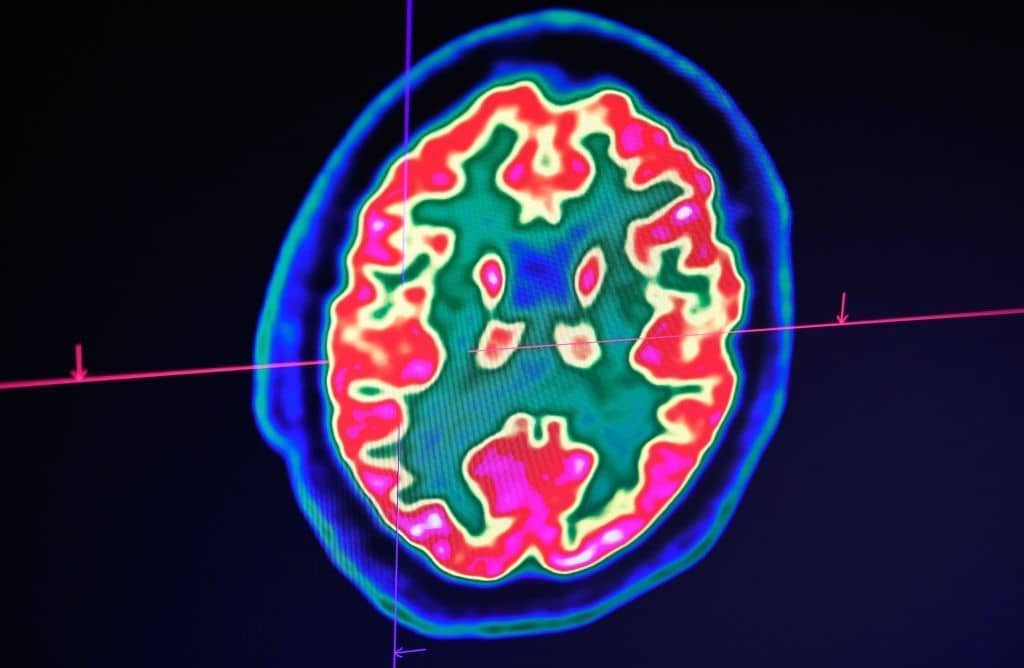

The last few years have seen a number of remarkable neuroscientific breakthroughs. In one study, scientists managed to communicate with a paralysed patient simply by asking him to imagine handwriting his thoughts. When he did so, brain implants recorded electric signals in his motor cortex, which artificial intelligence subsequently decoded with 94 per cent accuracy. In another, scientists tracked the ‘progress of a thought through the brain’: participants were asked to think of an antonym of a particular word, and electrodes planted on the cortex revealed how each step of the process — stimulus perception, word selection, and response — was ‘passed around’ to different parts of the brain. And in one landmark study, scientists claimed finally to have located the three specific areas of the brain — those linked to ‘arousal’ and ‘awareness’ — involved in the formation of consciousness.